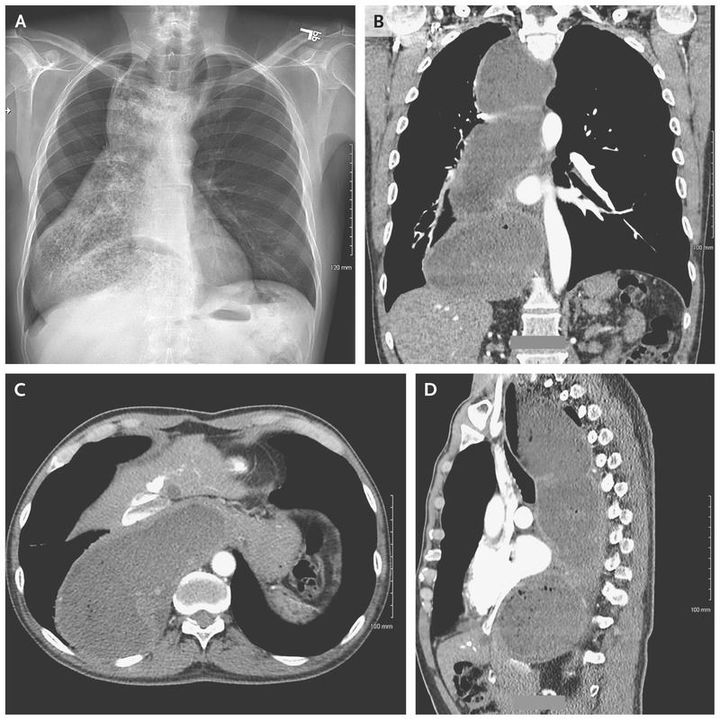

A 63-year-old man with a history of hypothyroidism presented with a 10-year history of dysphagia to solid foods and liquids. He had had worsening of his symptoms for 6 months before presentation, with an associated weight loss of 27 kg (60 lb). An anterior–posterior radiograph of the chest obtained on admission while the patient was in the upright position showed a mediastinal structure with internal debris (Panel A). Computed tomographic imaging revealed food extending from the proximal esophagus to the esophagogastric junction (Panel B shows the coronal scan, Panel C the cross-section view, and Panel D the sagittal view). Esophagogastroduodenoscopy revealed a dilated esophagus with food, and no strictures or masses were identified. The patient received a diagnosis of achalasia causing megaesophagus. Achalasia is caused by impaired relaxation of the lower esophageal sphincter and typically manifests as dysphagia to both solid foods and liquids. The patient underwent esophagectomy with a gastric pull-through procedure, and a jejunal feeding tube was placed. Eight months later, he had good oral intake and the tube was removed.